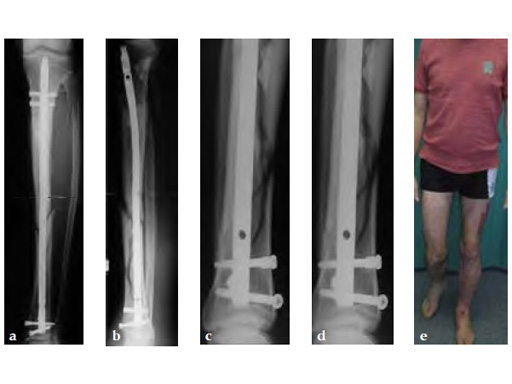

A 58-year-old male sustained a closed multifragmentary 42-C1 fracture in the distal tibia with compartment syndrome.

Case provided by Dankward Hntzsch, Tbingen, Germany

Primary treatment consisted of an external fixator and release of compartments.

Mobilization of the limb started with an applied external fixator.

Secondary treatment: insertion of an unreamed intramedullary nail with three ASLS screws inserted distally providing angular stability.

Partial weight bearing started on postoperative day 2 (with 2030kg). The weight was gradually increased over the following weeks. At 6 weeks, the patient was able to fully bear weight even though a high fibula fracture was present and no callus had yet formed. This suggests that angular stable interlocking of the nail markedly enhances stability. The patient was able to bear weight faster than planned and full weight bearing was possible with little pain.

Twelve-week follow-up shows callus formation, and the patient was able to fully bear weight without any pain.

The nail was removed 15 months postinjury as planned. There is good callus formation and proper healing of the tibia fracture.